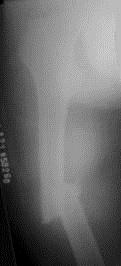

问题 病历摘要: 患者×××,男性,34岁,车祸致伤右大腿后肿胀、疼痛、畸形,活动受限2小时。查体:右大腿肿胀,成角畸形,骨连续性中断,右足背动脉搏动存在,右足伸屈功能正常。 该患者的正确诊断是: 提示: 患者 X线片如图:

选项 A、右髋关节脱位 B、右股骨干骨折 C、右股骨髁上骨折 D、右股骨中段骨折 E、右股骨干病理骨折 F、右股骨干骨肿瘤 G、右股骨粗隆间骨折 H、右股骨颈骨折

答案 D